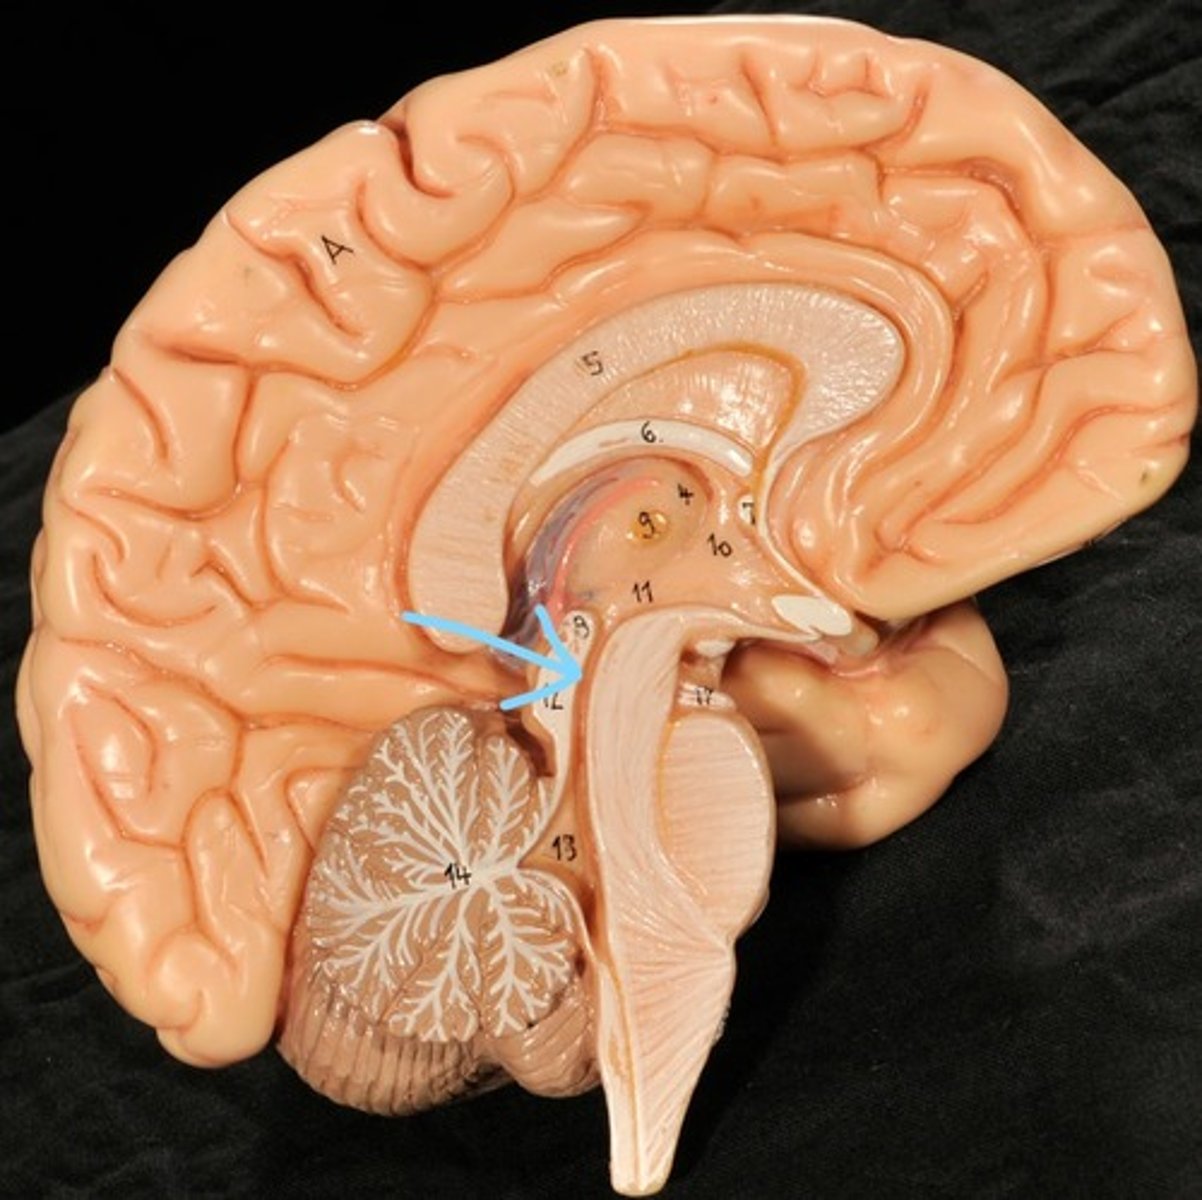

Identify structures of midsagittal brain

Corpus callosum

Diencephalon

thalamus, third ventricle, hypothalamus, epithalamus

Thalamus

Third Ventricle

Hypothalamus

Epithalamus (pink line)

Brain stem

Pons

Medulla oblongata

choroid plexus of third ventricle

produces cerebrospinal fluid

Third ventricle

cerebral aqueduct (midbrain)

midbrain

Fourth ventricle

Central Canal of brain

Takes Cerebrospinal fluid down to the spinal cord

Thalamus